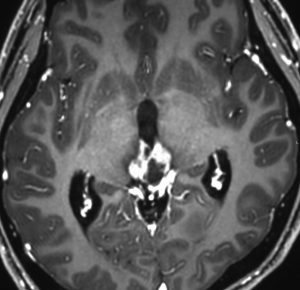

germinomaの視床浸潤:ミッキーマウスの耳

松果体ジャーミノーマは両側視床に浸潤して視床浮腫を生じます。真ん中に第3脳室後半部の割れ目が残っているのが特徴的な所見です。ミッキーマウスの耳みたいになります。かなり特異的な所見であり診断に有用です。右下は治療後です。